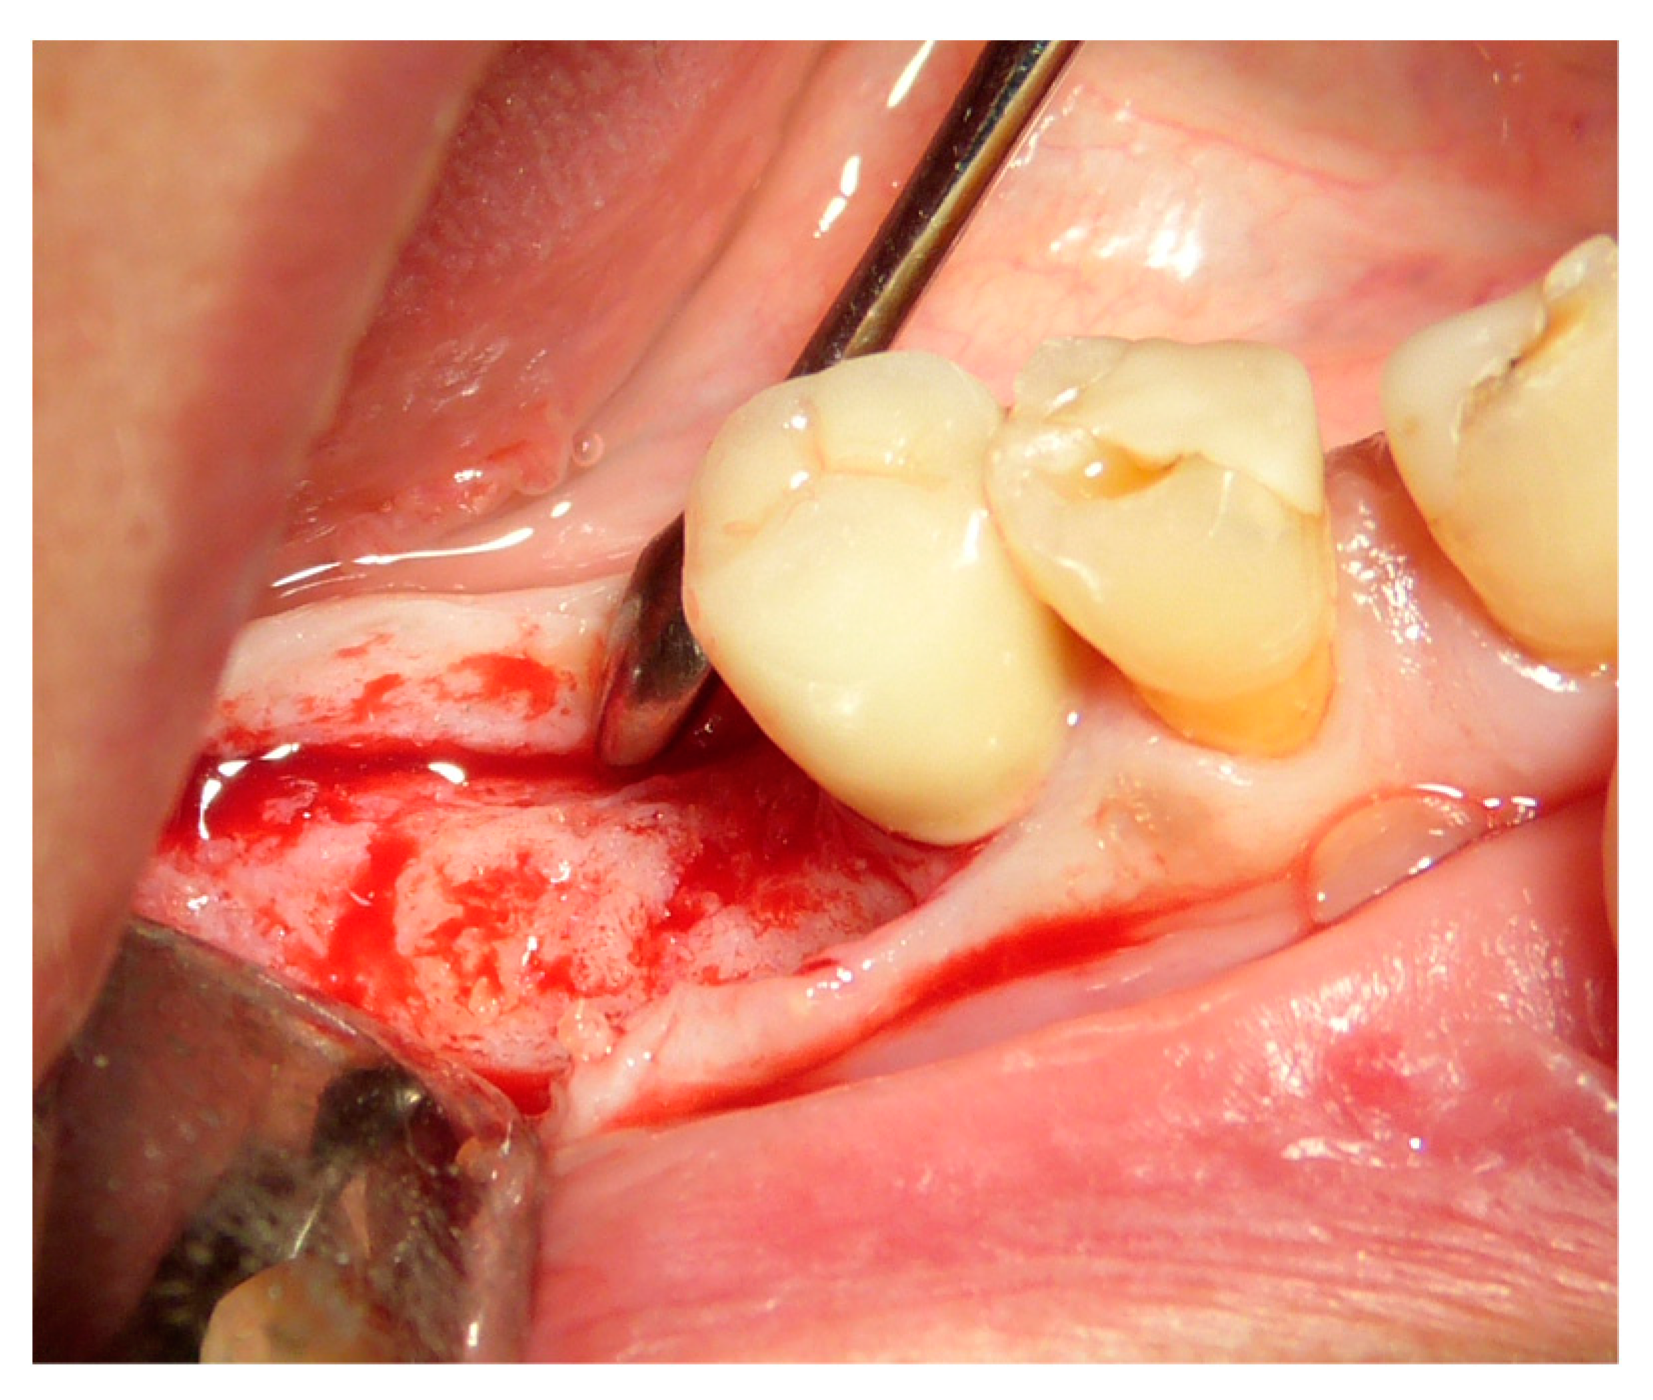

2.5. Surgical Procedures and Follow-Up